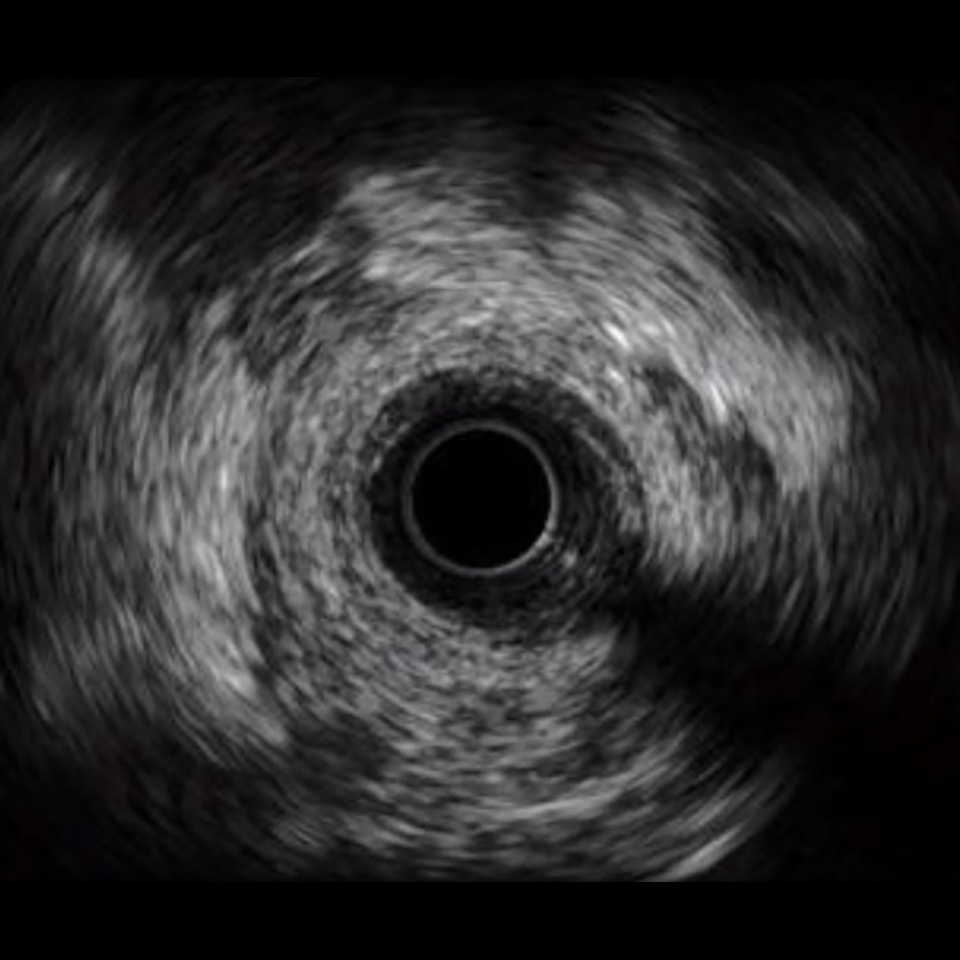

Philips Volcano Eagle Eye Platinum Imaging Catheter 20MHz

IVUS image of inside a coronary vessel using the 20MHz Philips Volcano Eagle Eye Platinum catheter

Axial resolution: <170 µm